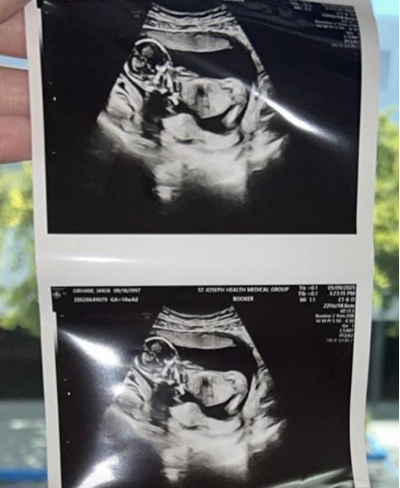

該名男子在IG限時動態中表示,醫師建議進行多項檢查及兩次回診,每次費用約380美元(約新台幣1.1萬元),但他全數拒絕,宣稱若真有問題醫師不會讓他出院,還說這些檢查只是「賺認知落差的錢」。此番言論讓許多網友看傻眼,質疑他身為準父親卻對新生兒健康如此輕忽。此外,他分享超音波照片時,還留言寫道「醫師說他屁股翹很高,不會生了一個_吧」,不當用詞遭網友怒批噁心至極。